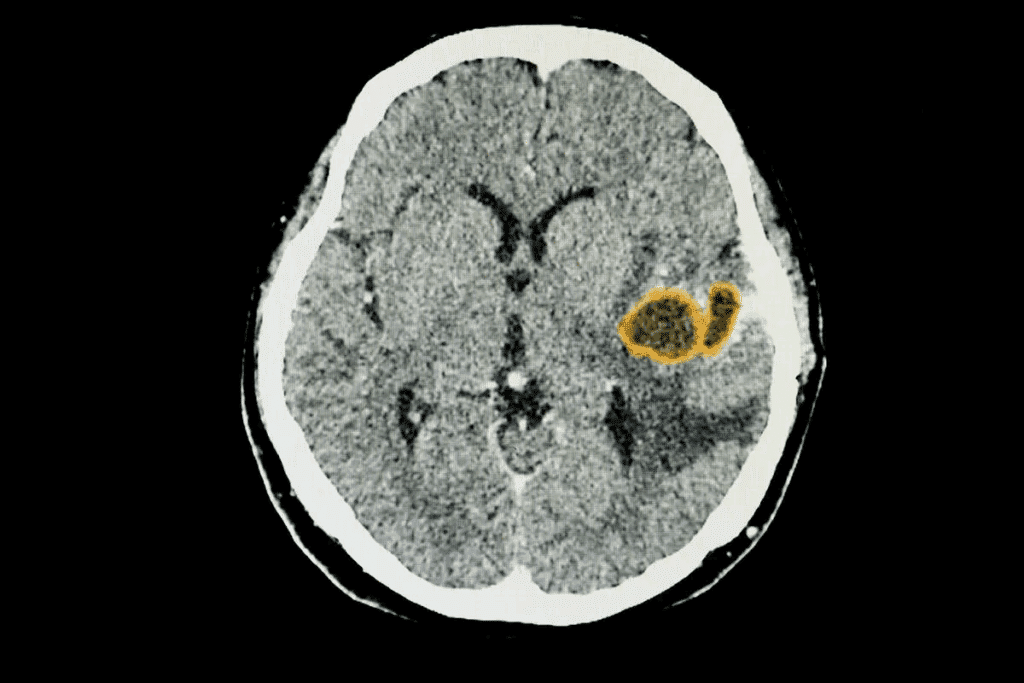

Imaging Techniques

Imaging is key in finding brain tumors. We use different methods to see the tumor’s details.

- Magnetic Resonance Imaging (MRI): MRI is top for finding brain tumors. It shows the brain clearly and tells us about the tumor’s size and where it is.

- Computed Tomography (CT) Scan: CT scans are good for quick checks. They show the tumor’s size and where it is.